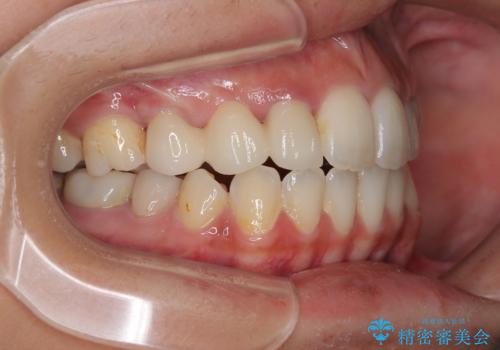

開咬と前突を改善 ワイヤー装置での抜歯矯正

結果として下顎の小臼歯は抜歯せず、右上の抜歯スペースはむし歯処置を兼ねてオールセラミックブリッジにて補綴治療を行うこととしました。

動かない歯での停滞や、出産と子育てなどにより治療期間は長期化しましたが、整った歯列にて仕上げることができました。